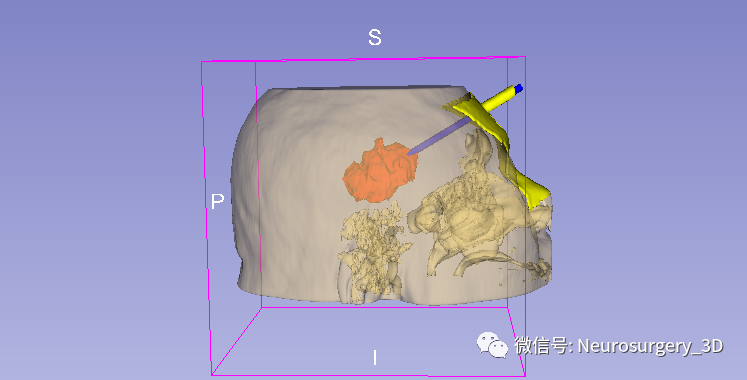

1、利用Ruler测量出穿刺血肿靶点至穿刺外口的距离,并设计出穿刺路径顺血肿长轴走形在血肿中心(并非如下图所示所有穿刺路径均与矢状面平行、请注意穿刺深度),避开颅内重要结构如额窦、上矢状窦等。

入颅点避开了额窦、上矢状窦

4、生成穿刺导板面具

5、修剪需要打印的穿刺导板